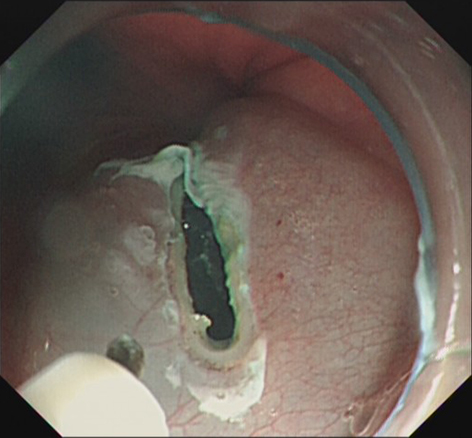

【2016年第6期】内镜超声引导下细针抽吸术治疗肝左叶囊肿的初步应用

近期我们为 3例患者成功实施了EUS引导下肝囊肿穿刺抽吸+硬化剂注射术治疗(超声主机 HITACHI EUB-5500,超声胃镜PENTAX EG-3830UT,穿刺针COOK ECHO-3-19,硬化剂:1%聚氧乙烯月桂醇醚(Lauromacrogol,聚桂醇)注射液,国产陕西天宇制药,国药准字:H20080445),现报道如下